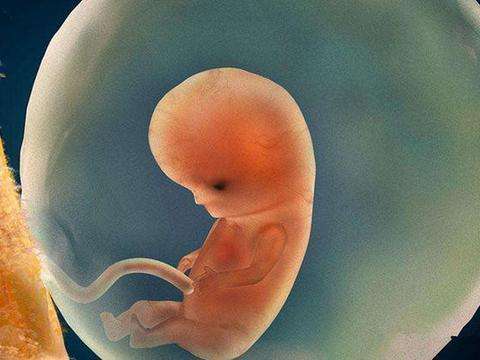

1、月份小的胎儿

对于月份很小的胎儿,一般在流产时都采取药物的方式,用药物将胎儿“扼杀”在女性的腹中,然后再排出女性的身体。这种被排出的胎儿,最终归宿就是流进了马桶里,随着旋转的抽水被带进了下水管、地下水道,再也看不见。